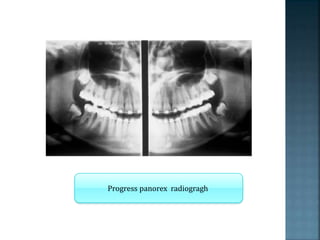

Pretreatment panorex radiogragh

Progress panorex radiogragh